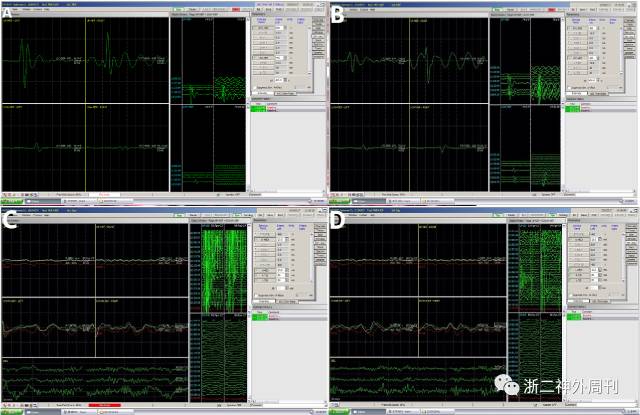

各项术前准备完善后,在电生理监测下行延髓髓内肿瘤切除术。患者取前冲俯卧位,三点头架固定,以C1为中心取约10cm直切口,暴露枕骨及颈1-2椎板,磨钻铣刀铣下枕骨约2cm*2cm,开放枕骨大孔,铣下C1-2椎板,显微镜下切开硬膜及蛛网膜,见延髓-C2水平脊髓膨大明显(图2),沿后正中锐性切开脊髓及延髓,显露肿瘤,呈灰褐色,质地中等,血供一般,尾端与脊髓边界清晰,延髓腹侧部分边界欠清,先以CUSA吸引器行瘤内减压后,显微镜下控制出血、仔细辨别肿瘤界面,电生理监测下(图3)全切肿瘤, MEP、SEP监测未见明显改变,提示脊髓功能保护良好。切除靠近延髓腹侧肿瘤时心率及血压出现一过性下降(图4),暂停操作后缓解。术后患者带气管插管送NICU,术后第二天拔除气管插管,患者四肢肌力5级,肢体感觉稍麻木,无呼吸及吞咽障碍。术后病理为室管膜瘤(WHO II级)(图5)。出院前复查MRI未见肿瘤残留(图6)。术后1周患者步行出院。

图3. 术中电生理监测,双上肢及双下肢运动诱发电位(MEP)在术前(图A)及肿瘤全切后(图B)均可引出;感觉诱发电位(SEP),术前(图C)及肿瘤全切后(图D)双上肢均未引出,双下肢在术前术后均可引出,无明显异常。

图4. 切除靠近延髓腹侧肿瘤时心率及血压出现一过性的下降。